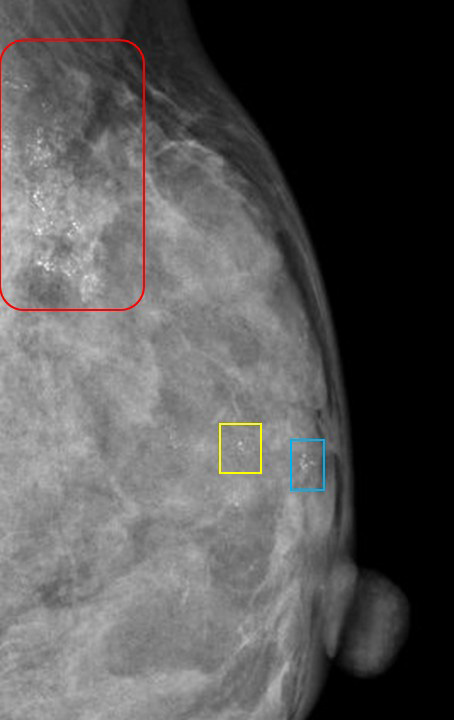

(実際の画像)

前医では、なんと(赤枠で囲った)main lesionの他に(その中枢側に)「黄色枠」や「青枠」の部分の石灰化を「多発=温存不可」と説明していたのです!

明らかにこれら(「黄色枠」や「青枠」)は「赤枠」と同じ乳管系の「中枢」にできた石灰化であり、多発ではなく「同一乳管系の複数の石灰化」と呼ぶべきものだったのです!

その施設で行われた(そして癌の診断にいたった)ST-MMTの画像も(セカンドオピニオンの資料として)ついていたのですが…

ST-MMT画像① 針を引き抜いた際の撮影画像

なんと!(そのST-MMT画像で)石灰化を外していたのです!

私の正直な感想として…

これだけ広範囲に存在する「狙いやすい石灰化」をわざわざ?外すんかい!(関西風に)

ST-MMT画像② 摘出した標本撮影

最初、この画像を見たときは「あれっ?石灰化無いな。それじゃー(他に)石灰化が採れている画像もあるのかな?」

しかし、ファイルを探せども標本画像はこれだけだったのです。

♯確かに①画像を見れば「上手いこと?」石灰化を外しているわけですが…

ただST-MMTは「石灰化を採取する」のが目的なのだから、通常ならば患者さんに

『残念ながら1回目は石灰化が採取できていなかったので、もう一度やりますね』

と承諾いただいて、2回目にトライして「今度は石灰化取れました。それでは終了です」とするのが常識だと思うのだが…

何故か、これで終了している。何故?

ただ(患者さんにとって)大変幸運なことに「石灰化が無い標本にも癌細胞が存在しており(全ての癌組織が石灰化を起こしているわけではないので石灰化を起こしていなかった癌組織が「たまたま」採取できていたということ)

それは(セカンドの資料として添付されていた)病理診断を見ても確認しました。

♯石灰化の記載が一切ないのです。